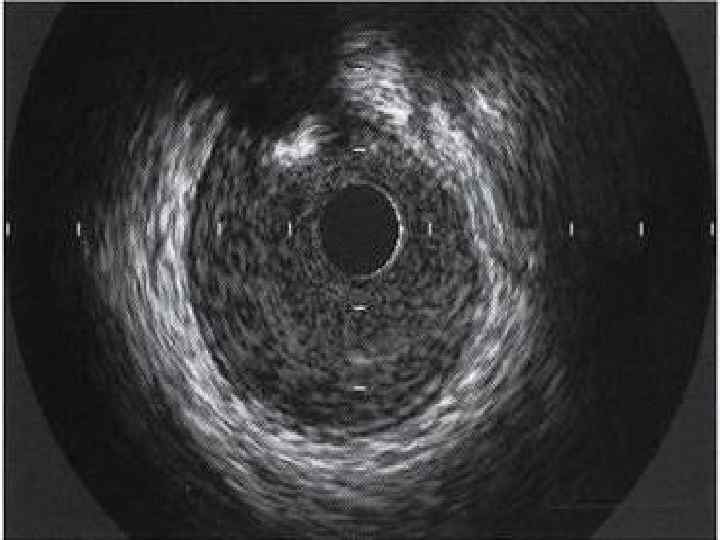

Виды эхокардиографии • Трансторакальная ЭХО КГ • Чреспищеводная ЭХО КГ • Стресс ЭХО КГ • Контрастная ЭХО КГ • Интраоперационная ЭХО КГ • Внутрисосудистая ЭХО КГ